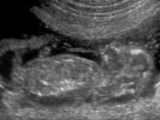

La gestation chez la chienne induit de nombreux bouleversements dans son organisme dont il va falloir tenir compte pour adapter au mieux son alimentation. Durant la première moitié de sa grossesse, il importe de lui fournir une nourriture plus riche en nutriments sans pour autant augmenter le nombre de calories habituel. La seconde moitié impliquera en revanche une augmentation progressive de la ration en calories.